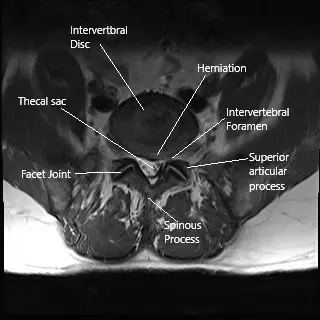

MRI axial section of the lumbar spine showing foraminal stenosis.

MRI of the lower spine revealed an L4-L5 diffuse disc bulge with superimposed right central

subarticular and foraminal disc protrusion (disc herniation) and intermediate-grade central canal and high-grade foraminal stenosis, right greater than left. There is an L5-S1 shallow left central and subarticular disc protrusion (disc herniation).